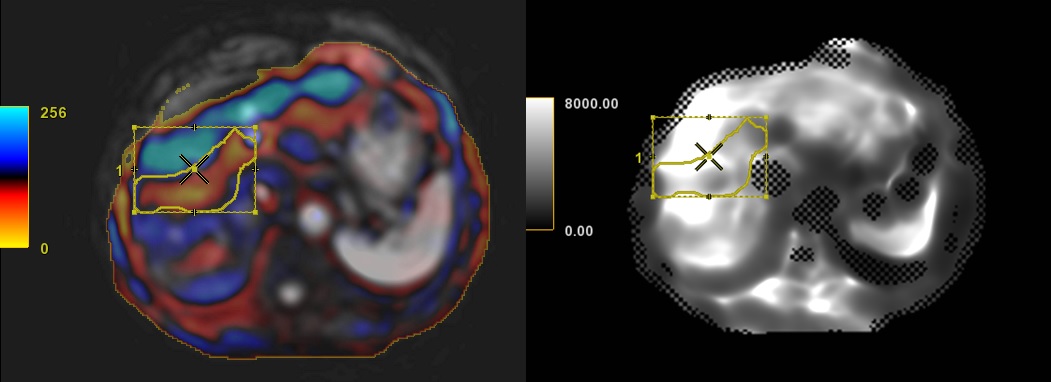

Figure 6. Note that the ROI is one wave (in this example, the first wave is blue) away from the surface of the liver and does not include any masked regions.

- Copy the edited ROI from the anatomic image and paste it onto the gray scale non-mask image.

Figure 7. ROI copy/pasted from a reference to gray scale non-mask image

- Repeat this step for each ROI on other slices, as needed.

Important: The masked regions or checker box areas indicate the wave propagation was not sufficient to confidently generate stiffness contrast. Including masked (checkerbox) areas in your ROI will skew the ROI statistics. Failure to place the ROI as described will negatively impact the output measurement.